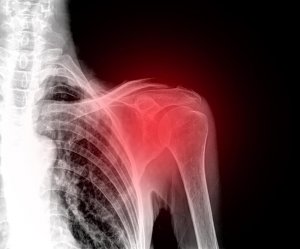

Axelvärk är ett mycket obekvämt tillstånd som gör att du blir handlingsförlamad eftersom det gör att du inte kan interagera effektivt med din omgivning. Det finns olika typer av skador som kan orsaka axelsmärta och svullnad. Du kan till och med drabbas av kronisk svullnad om du inte får någon medicinsk behandling.

Först och främst är det värt att veta att axelvärk är vanligare än du tror. Självklart behöver du uppsöka läkare om något går ur led eller om du drabbas av frakturer. Dessa två situationer är i allmänhet resultatet av ett trauma inom axelpartiet.